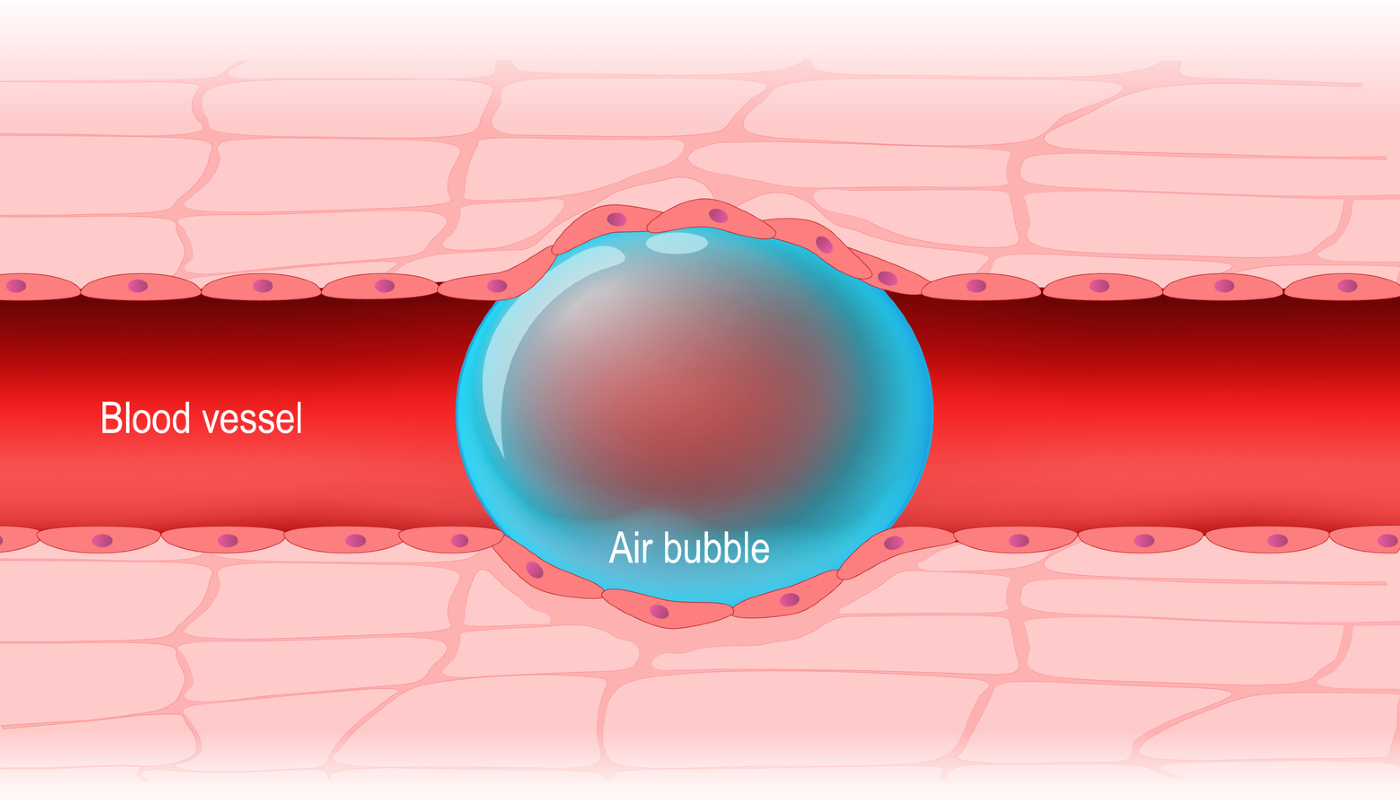

De acordo com os boletins médicos divulgados ao longo da internação de Paulo Gustavo, o ator apresentou, após uma breve melhora, um quadro de embolia gasosa que afetou seu sistema nervoso central e tornou a situação irreversível. Segundo a médica de CTI Nathalia Fortins, professora da plataforma Jaleko, embolias são quadros nos quais algo que não se dissolve no sangue provoca a obstrução de um vaso sanguíneo – e, no caso da gasosa, este material é o próprio ar.

Apesar de necessário para o organismo, o ar não entra na corrente sanguínea livremente; após a inspiração, os alvéolos (estruturas que existem aos milhões nos pulmões) se encarregam de transferir o oxigênio para o sangue, enquanto o gás carbônico faz o processo inverso e é expirado. Em casos como o de Paulo Gustavo, porém, o ar acaba circulando livremente nos vasos em forma de bolhas – algo que interrompe o fluxo sanguíneo em órgãos vitais ao viajar pelo corpo.

Ao longo do tratamento, Paulo teve fístulas broncopleurais (entre uma estrutura interna do pulmão e a membrana que o reveste). Elas foram inicialmente sanadas, mas uma nova ruptura (a fístula brônquio-venosa, entre a mesma estrutura anterior e uma veia) foi responsável por permitir esta passagem de ar. Devido à obstrução causada pelas bolhas em vasos importantes, a embolia gasosa impede o sangue de chegar a determinados órgãos, levando-os, por isso, à falência.

Apesar de compartilharem um nome, a embolia gasosa e a tromboembolia não são a mesma coisa. Isso porque, na gasosa, há obstrução de vasos sanguíneos por bolhas de ar e, na tromboembolia, esta obstrução de vasos ocorre por conta de coágulos. Enquanto no segundo caso é possível muitas vezes utilizar medicamentos para dissolver os coágulos, não há remédios que possam retirar o gás da corrente sanguínea.